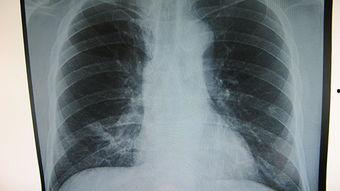

首先,让我们来了解一下肺部吸痰的基本概念。肺部吸痰,顾名思义,就是通过特定的工具,将肺部内的痰液吸出来,以保持呼吸道的通畅。这个过程对于患有呼吸道疾病、手术后的患者,或者是长期卧床的老人来说,尤为重要。

你知道吗?肺部吸痰不仅可以清除呼吸道内的痰液,还能预防肺部感染,改善呼吸功能。对于那些无法自主咳嗽的患者,肺部吸痰更是必不可少的护理措施。